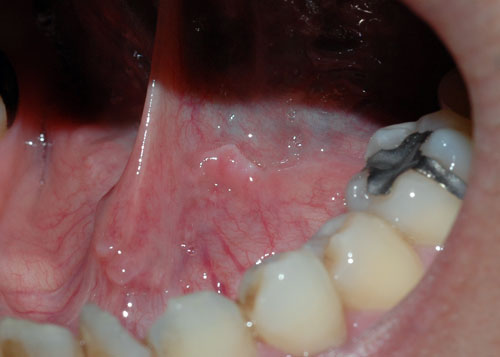

口腔内の尖圭コンジローマ?: STD・性行為感染症。